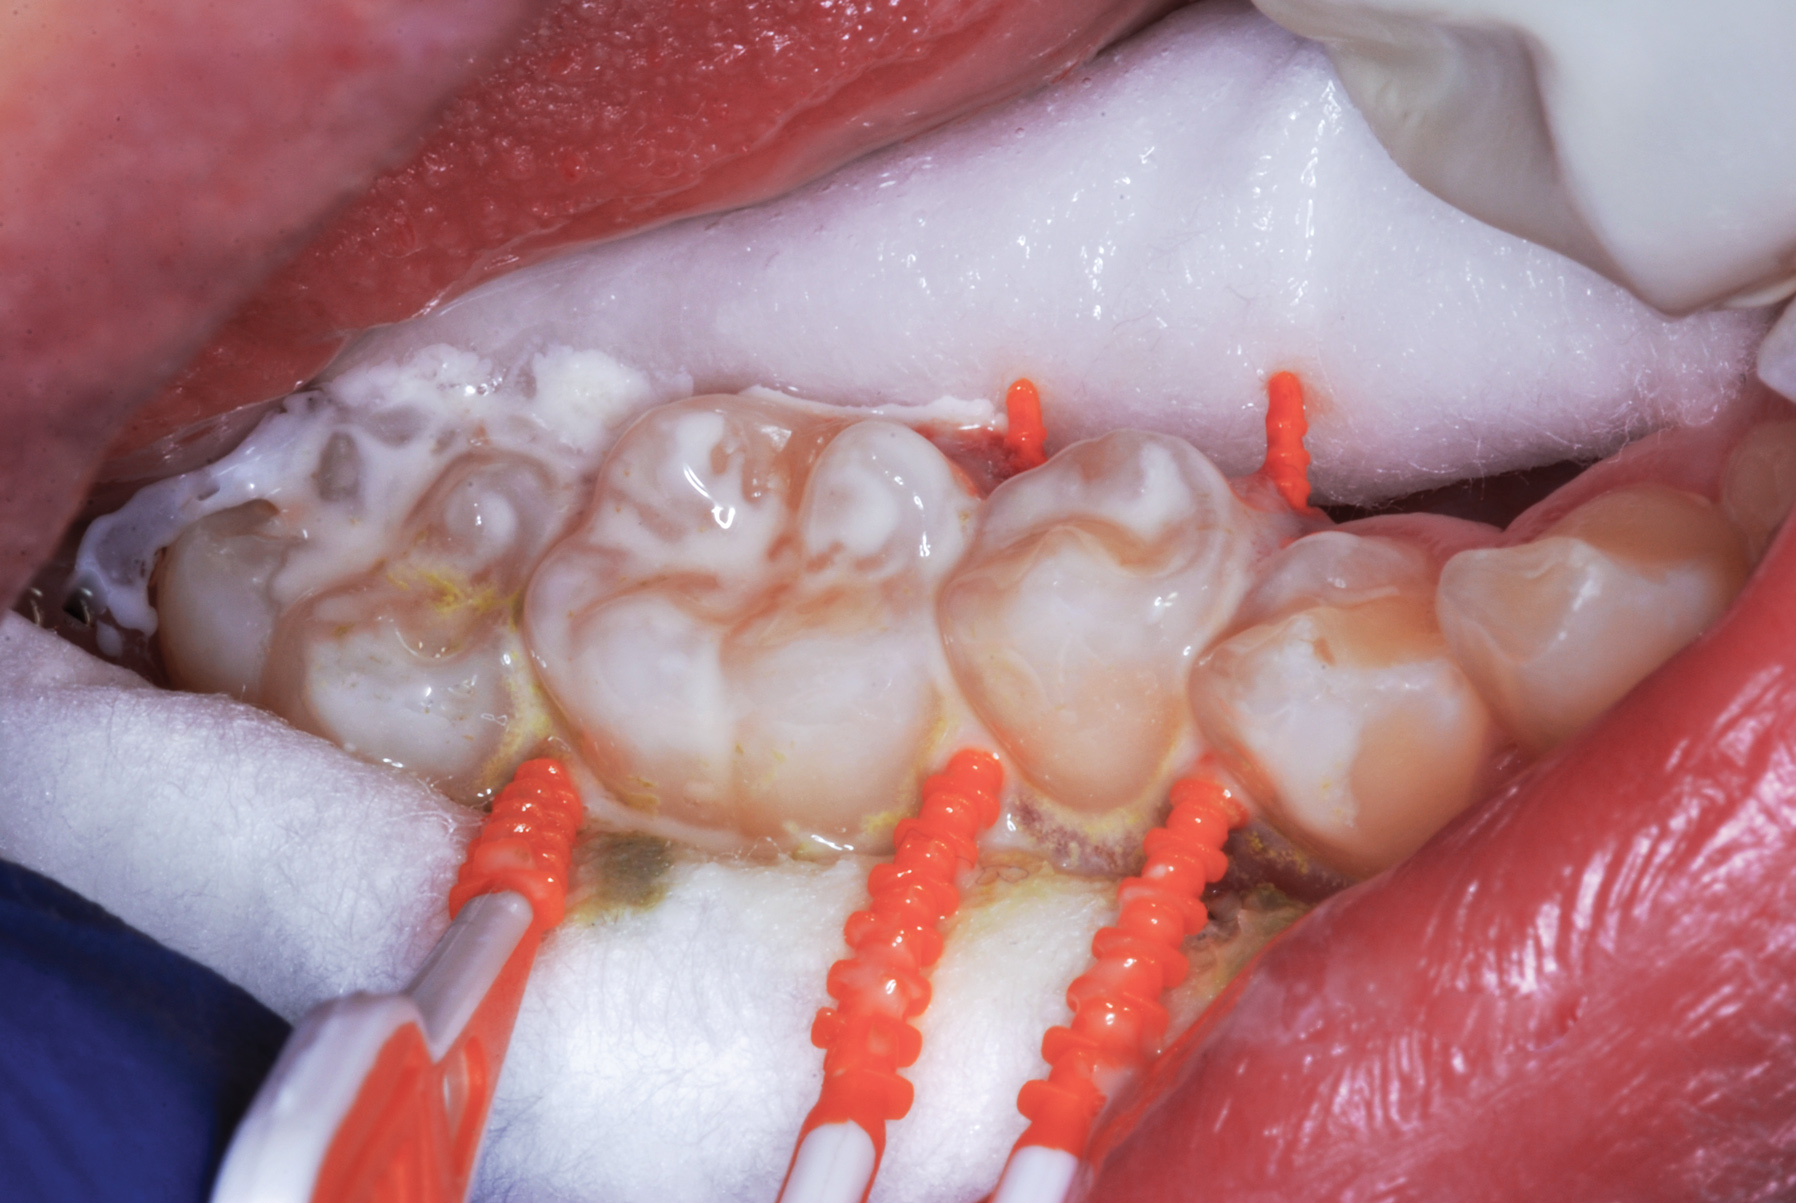

The authors' protocol for insertion of SDF-coated soft dental picks involves isolating the teeth with cotton rolls or other means, flossing the interproximal site to clear food debris and dental plaque, and then inserting a SDF-coated pick (Figure 1 and Figure 2) to saturate the contacting surfaces of the teeth with the fluid. This treatment is painless and requires no anesthetic. The pick should remain in place for at least 60 seconds and can be gently pulled in and out to agitate the fluid for enhanced surface coverage by capillary action. Additional SDF can be wiped on, using a small applicator, above the contact and in the buccal and lingual sluiceways. Excess fluid and any blood elicited may be blotted with a cotton swab. An additional 60-second insertion may be applied in the same way if there is radiographic evidence of a deeper decalcification or caries lesion. With the pick still in place, 5% (or 2.5%) fluoride varnish is painted over the treatment area, and the pick is then withdrawn.

Interproximal insertion of SDF is demonstrated in different patients in Figure 3 through Figure 11. Various diameters and brands of soft dental picks may be used depending on the closeness of the proximal surfaces and ease of insertion; for example, some picks are designed for use in wider spaces between teeth. This protocol also offers versatility. Figure 3, for example, shows the simultaneous use of three thin soft dental picks to saturate proximal surfaces with SDF in a teenaged patient; the treated regions were subsequently covered with fluoride varnish (Figure 4). This patient was initially treated in April 2019 (Figure 5), with an identical re-application 3 months later. As shown in Figure 6, the December 2019 bitewing film revealed good results with the possible exception of the contact regions of the maxillary first and second molars. New SDF application was completed in the December appointment.

Fig 3. Three thin soft dental picks were used simultaneously for SDF proximal surface saturations in a teenaged patient (Fig 3). After 60 seconds, the treated regions were covered with 5% fluoride varnish (Fig 4). A comparison can be seen of pre-SDF-treatment bitewing films (Fig 5) and 8-month post-SDF bitewing films (Fig 6) for the patient shown in Fig 3 and Fig 4. Radiolucencies were similar or improved, except for contact of maxillary first and second molars.

Figure 3

Fig 4. Three thin soft dental picks were used simultaneously for SDF proximal surface saturations in a teenaged patient (Fig 3). After 60 seconds, the treated regions were covered with 5% fluoride varnish (Fig 4). A comparison can be seen of pre-SDF-treatment bitewing films (Fig 5) and 8-month post-SDF bitewing films (Fig 6) for the patient shown in Fig 3 and Fig 4. Radiolucencies were similar or improved, except for contact of maxillary first and second molars.

Figure 4